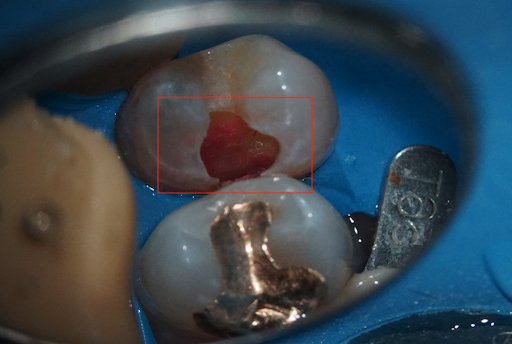

虫歯を染め出した状態(赤色の染色部分)

では、具体的な虫歯をとる治療についてご説明します。虫歯を発見するため、目で確認(色、穴など)、レントゲンで確認、虫歯検知液を使用してチェック、歯の硬さの確認を行います。

虫歯を発見できたら、虫歯菌に感染した歯を削っていきます。どこまで感染しているかを検査するのが虫歯検知液です。この検知液は、感染しているところのみが染まるようにできています。

この検知液を使いながら、また虫歯で脆くなっている部分はやわらかくなっているため硬さの確認も行い感染しているところのみをしっかりと除去しきることが大切です。これには、結構な時間がかかります。しかし、丁寧にこの治療をすることが歯の寿命を伸ばすことにつながります。

手前の歯(画像右手の歯)を治療中に、後方の歯にも虫歯を発見しました。

虫歯を表面除去したところ、深部まで進行していることを確認できました。